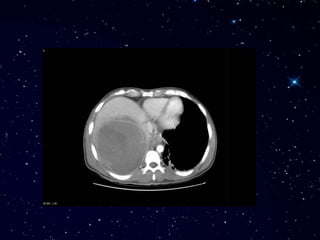

Зураг